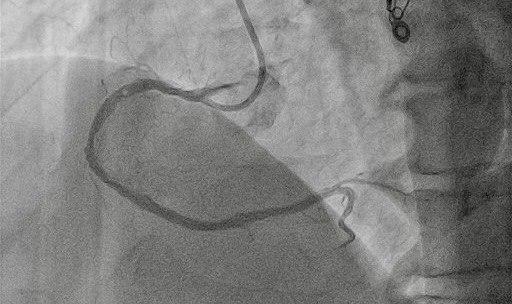

A Convey CLS 4 6F guiding catheter (Boston Scientific) was engaged in the left main coronary artery, and an Amplatz left 1 7F was engaged in the ostium of the RCA. Starting from the antegrade with a Gladius EX guidewire (Asahi) and a Turnpike Spiral microcatheter (Teleflex), a dissection reentry was attempted. Τhe Gladius EX, the Gaia Next 2 (Asahi), the Confianza Pro 12 (Asahi), and the Hornet 14 (Boston Scientific) were used consecutively, passing inside the outer layer of the vessel (adventitia), next to the old stent, and reentering in the distal part of the RCA. In order to reenter the true lumen before the bifurcation, a Stingray balloon (Boston Scientific) was used. A Gaia Next 3 was advanced inside the Stingray, successfully reentering the lumen. Afterwards, balloon inflation was performed throughout the vessel and, finally, 4 stents were deployed with a good angiographic result and Thrombolysis in Myocardial Infarction-III flow (Figures 1 and 2, Videos 1 and 2). The patient was discharged the next day.